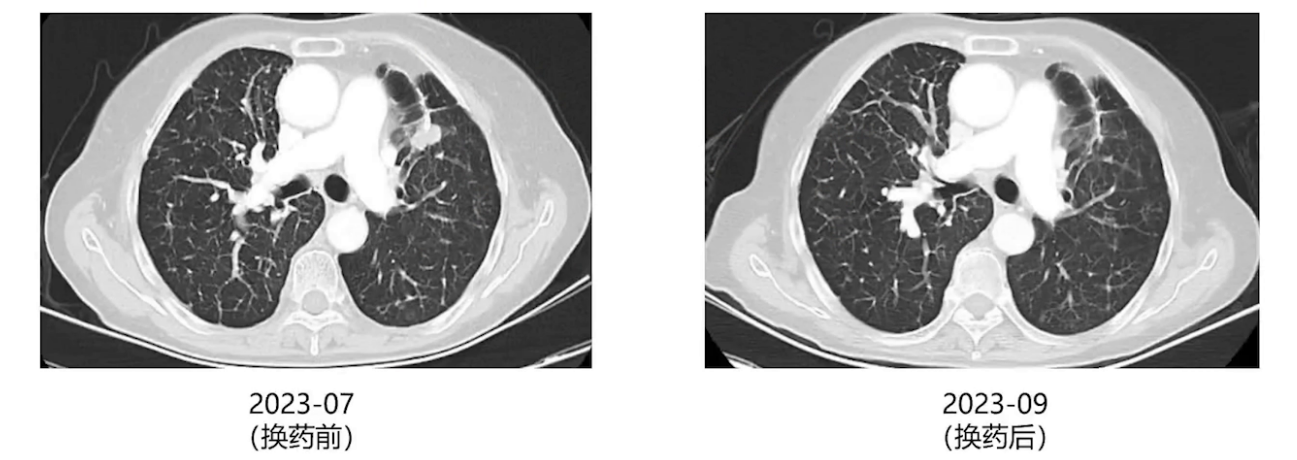

2022年5月开始左肺结节逐渐增大,2023年7月复查时结节明显增大,PET-CT检查全身评估后,经多学科讨论,因既往NGS检测提示MET扩增,考虑口服塞沃替尼靶向治疗后复查再评估是否放疗,8月开始奥西替尼联合塞沃替尼治疗,1个月后胸部CT复查,左肺增大的结节明显缩小。因治疗药物有明显消化道不良反应,9月改用氟美替尼联合塞沃替尼治疗,患者目前维持治疗,一般情况良好。